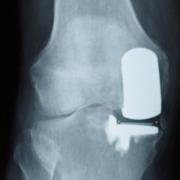

Tibiofemoral partial knee replacement, replacing one compartment of the joint.

This is an X-ray showing a tibiofemoral partial knee replacement. The metal shows up as white, and the gap between the two metalllic bits is the plastic spacer (which does not show up on X-ray).